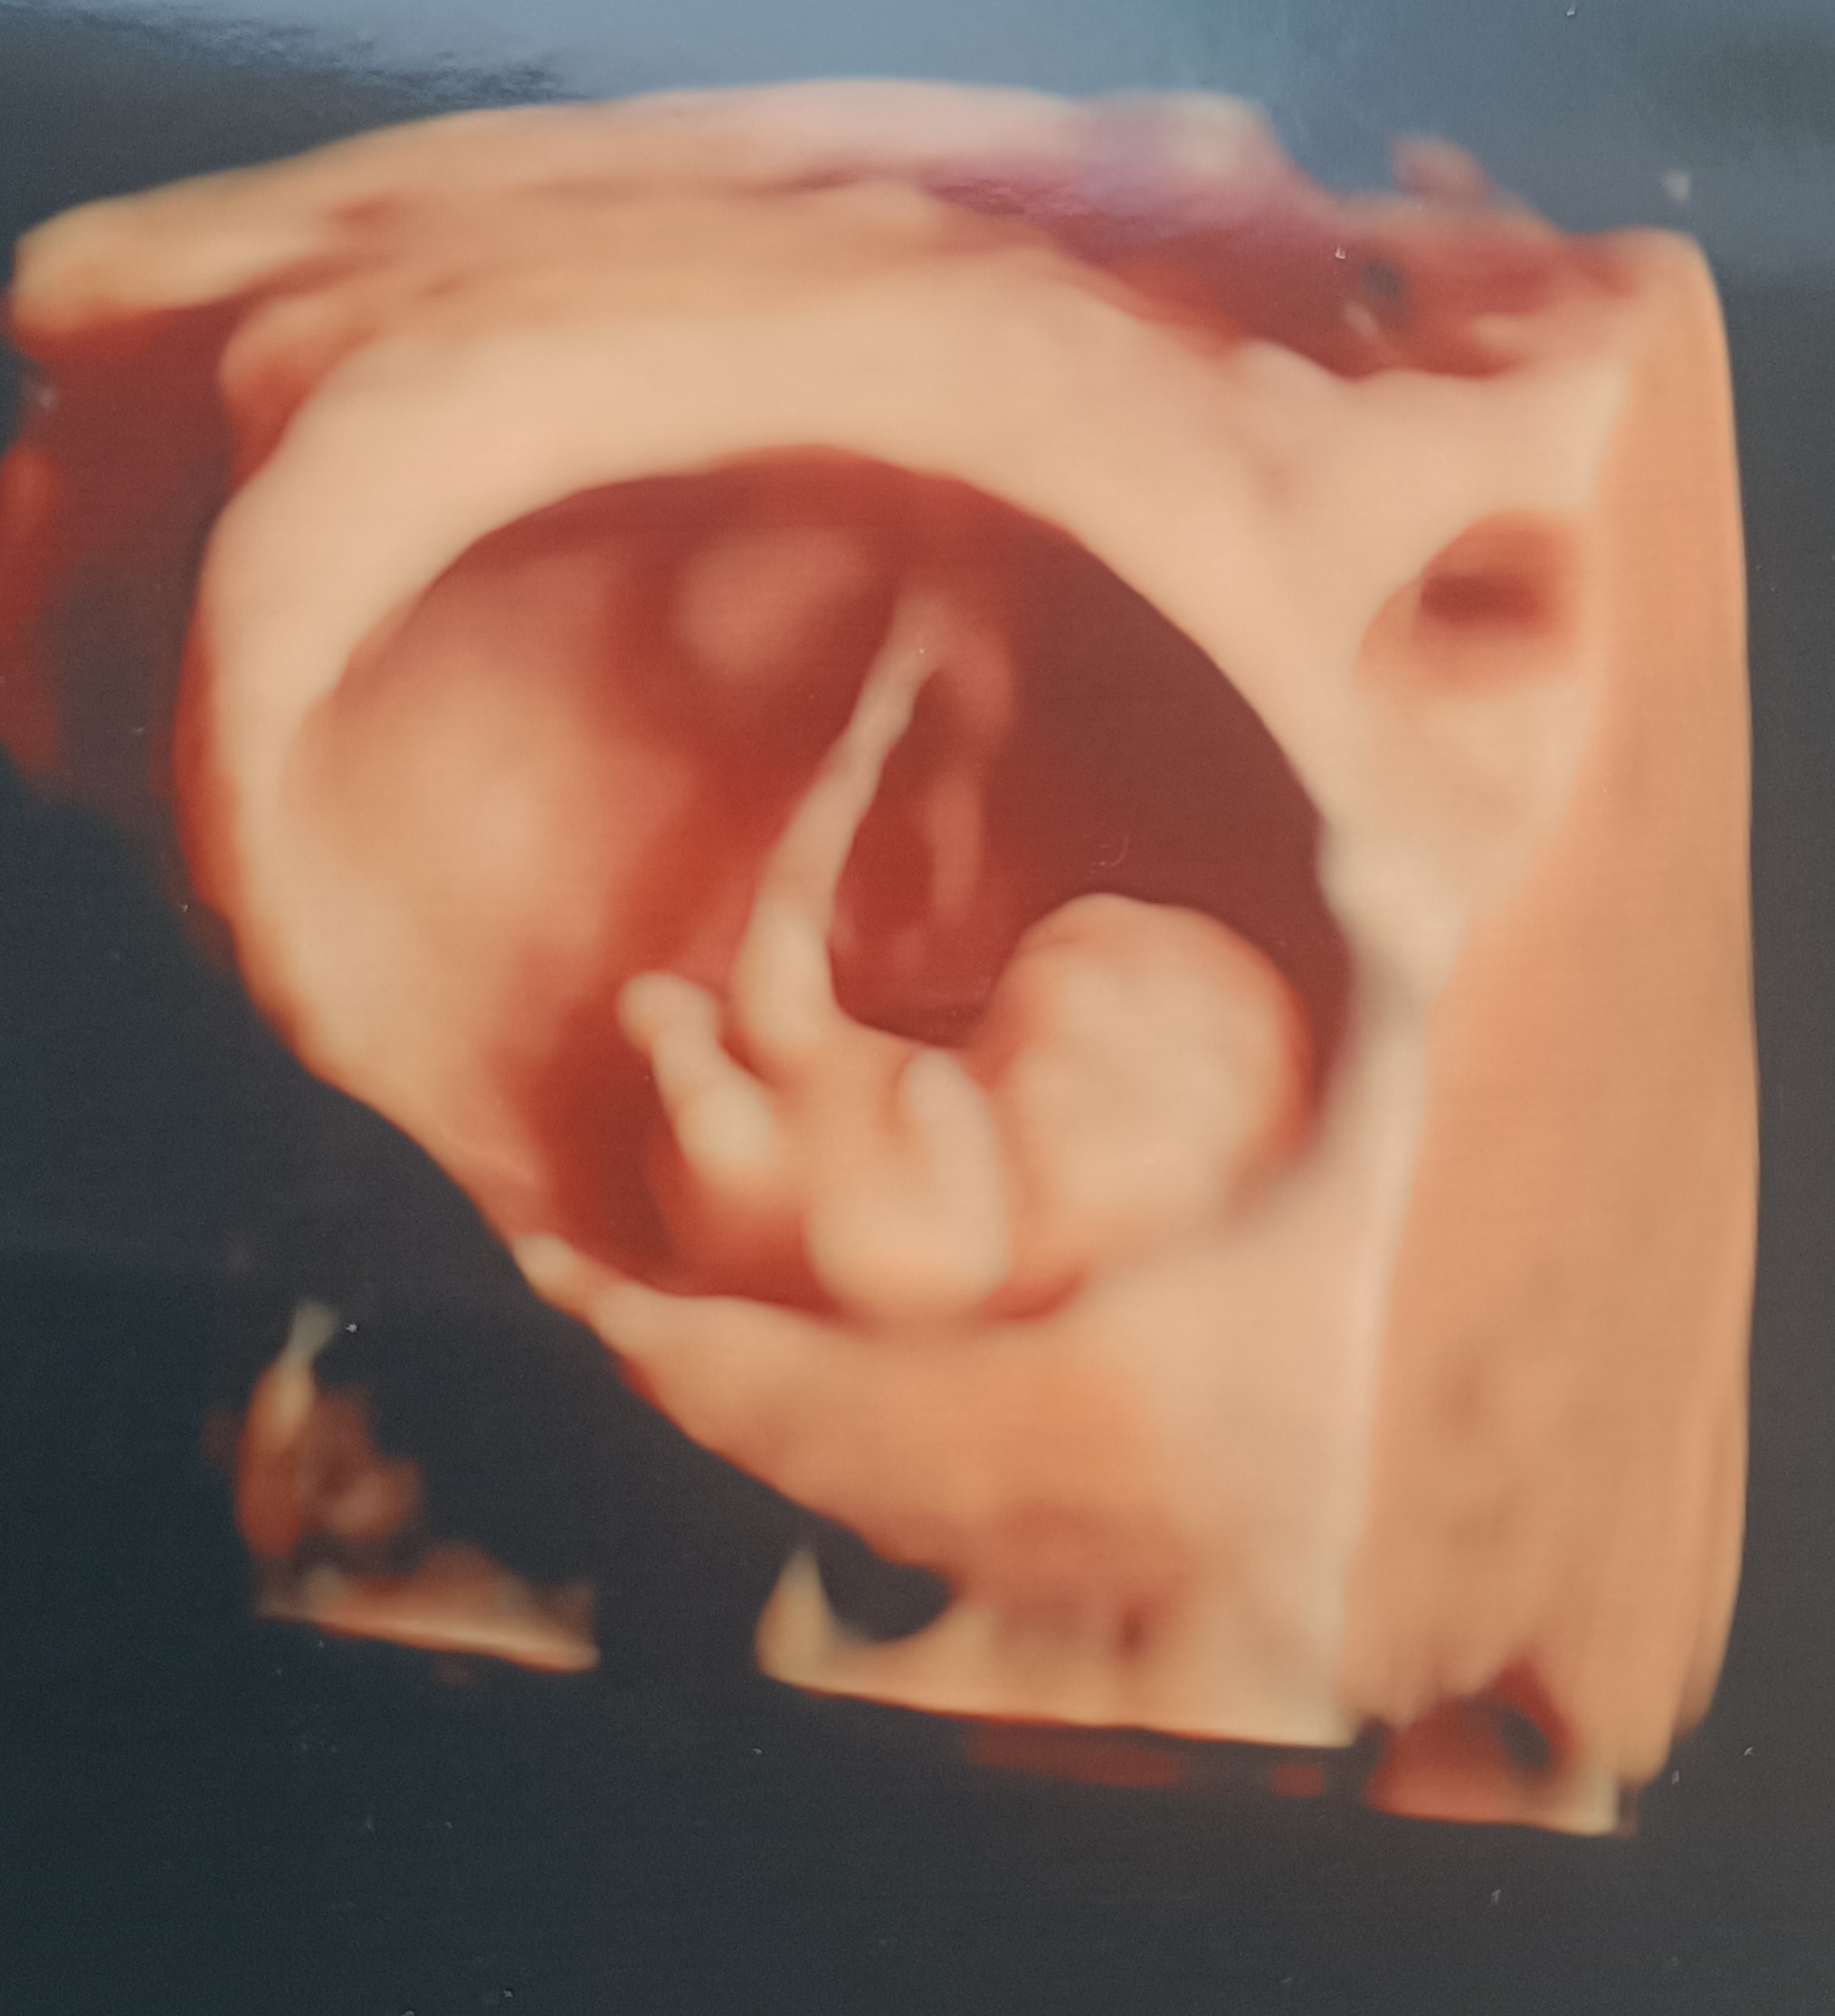

Ja już po drugim USG tym razem prywatnym 😎 2.25 cm szczęścia z pięknie bijącym serduszkiem 💓 8+6 - z USG idealnie bo już 9+0 ale mamy wieczór 🤣 więc książkowo 😍

Załączniki

• IMG_20230427_202554.jpg

IMG_20230427_202554.jpg

432,3 KB · Wyświetleń: 178